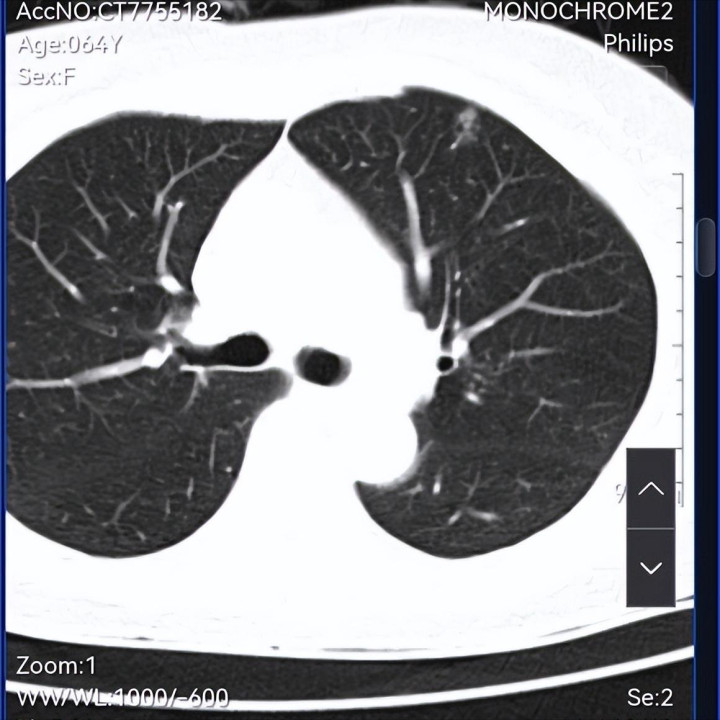

这几年体检发现多发结节,本年的是不是有变化了,是否需要手术,请咱们信任的戴主任会诊,是否不错传云影像可能看的更显着。九故十亲齐来这里请咱们信任的戴主任调理,期待着主任的会诊。